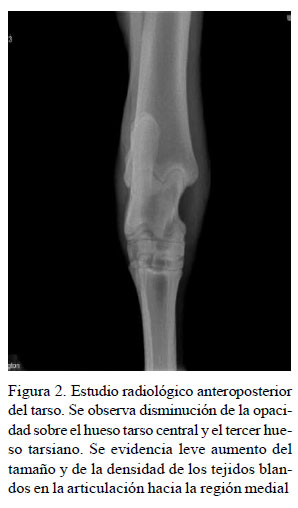

Ante los hallazgos obtenidos en la exploración clínica se hizo un estudio radiológico con vistas latero medial y anteroposterior del tarso izquierdo, encontrando incremento del volumen articular, aumento en el tamaño de la articulación del tarso e incremento en la densidad de los tejidos blandos periarticulares (Figura 2).

La efusión articular es un hallazgo común en articulaciones diartrodiales, las cuales se relacionan con procesos inflamatorios de origen agudo, generalmente asociadas a un evento séptico. La interpretación en el diagnóstico imagenológico permite determinar algunos cambios en el tejido. En el equino, a nivel de miembros posteriores, las articulaciones del tarso son las más afectadas, y a su vez, las que más se relacionan con claudicaciones (Vanderperren et al., 2009). Las estructuras sinoviales en el equino que pueden verse afectadas por sepsis son las bursas, las vainas tendinosas y las articulaciones sinoviales, siendo la tarsocrural la articulación más afectada (Taylor, 2010; Rinnovati, 2018).Así mismo, los hallazgos más relevantes en la evaluación radiográfica de un equino con artritis séptica tarsiana son la osteolisis de la porción distal de la tibia a nivel fisiario y epifisiario, acompañado del aumento de la densidad del líquido articular y de los tejidos blandos (Glass y Watts, 2017), lesiones que coinciden con el presente caso.

El diagnóstico imagenológico a nivel articular en equinos reviste gran importancia en la determinación de los posibles hallazgos. Hardy (2006) menciona que el estudio radiográfico en pacientes con artritis séptica permite correlacionar con los hallazgos clínicos presentes en el examen físico del paciente, a la vez que describe lesiones como disminución de la opacidad a nivel del hueso cortical, reacción perióstica exacerbada, aumento del tamaño y de la densidad de la cápsula articular, y aumento del líquido sinovial. Morton (2005) menciona, asimismo, que en pacientes adultos con historial de artritis séptica pueden encontrarse cambios articulares degenerativos debido a la erosión y posterior mineralización del cartílago articular, produciendo artrófitos o enteseofitos. En este caso en particular no se encontraron cambios degenerativos, ya que las lesiones presentes estaban más relacionadas con un estado agudo inflamatorio.